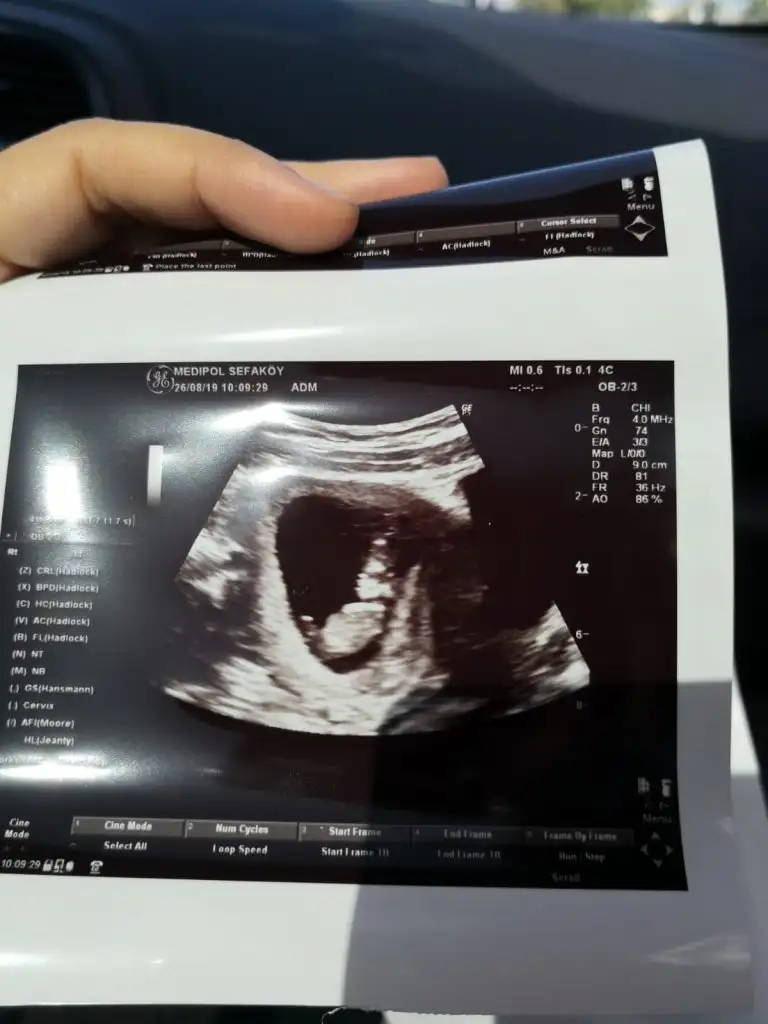

Teşekkürler haftaya kontrolüm var inşallah bu sefer gösterir. 2 kişi erkek dedi. Öğrenince yazarım buraya da :)Erkek gibi

Yazarsın bize hayırlı evlat olsun inşallahTeşekkürler haftaya kontrolüm var inşallah bu sefer gösterir. 2 kişi erkek dedi. Öğrenince yazarım buraya da :)

ErkekEki Görüntüle 2301494 Eki Görüntüle 2301495 Merhaba bende tahmin alabilirmiyim

ErkekSelam kızlar. 10+5 günlük hamileyim, var mı bi tahminleriniz